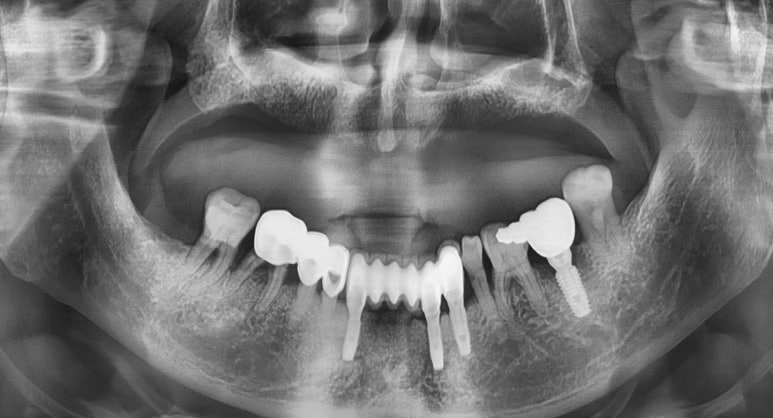

처음 내원하여 치료 받기 전 사진

![[남대문] 치과임플란트 조금더 덜아프고, 간단하게! 관련 이미지 4](https://pub-9f2bb3498faf4d1d8714b41df24753e3.r2.dev/content/clinics/archive/rseeanjxfu/naver_blog/yonseiyegam/assets/by_hash/442cc5e177ff55b1819cc995104a3131316c21aeee32d63478d9b3708821d7eb.jpg)

이렇게 위아래 야매 틀니를 하고 계시던 분이 저희 연세예감치과를 방문하셔서

겁이 많아 위 틀니만 새로 하시고 빠진 이는 그대로 놔두셨는데

아래 어금니 네비게이션 임플란트를 해보시고는

아무렇지도 않고 수술한 느낌도 안난다며,

아래 앞니도 네비게이션 임플란트 진행하셨습니다.